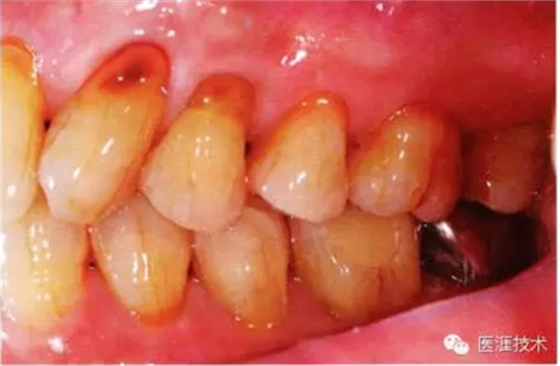

44歲牙周炎女性的臨床照片

44歲患有糖尿病病史(未治愈)。菌斑控制不良。通過(guò)牙周探診,全頜有4~8mm的牙周袋,在X光片中可以看到上頜前牙處中度牙槽骨吸收,磨牙處重度牙槽骨吸收。二次齲齒和根面齲齒也有發(fā)生。可以看到浮腫性腫脹,收到刺激后會(huì)出血。